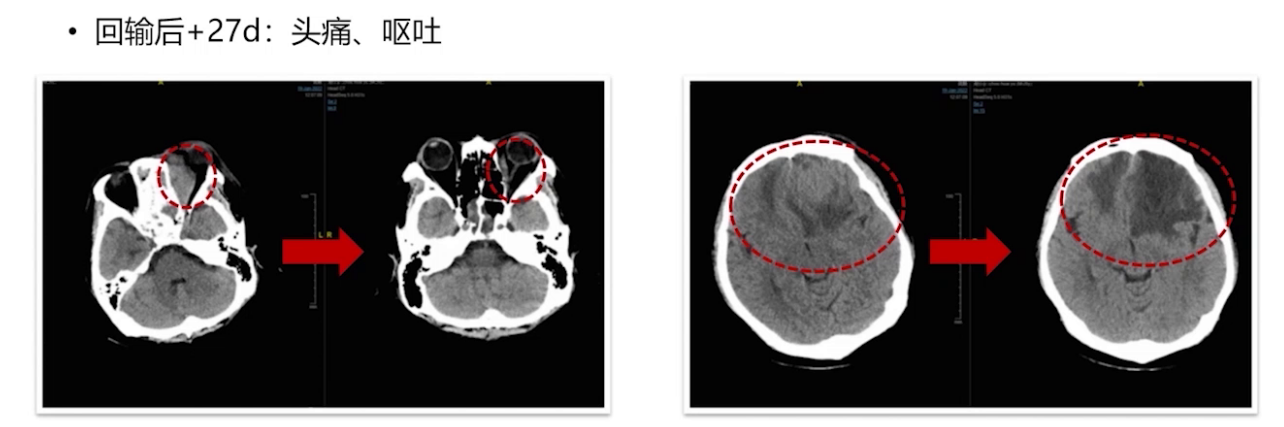

2021年12月21日进行CAR-T细胞单采,22日开始桥接治疗(MTX联合BTK抑制剂),2022年1月7日进行FC预处理化疗,1月12日回输CAR-T细胞。治疗后出现发热CRS 2级反应、意识障碍,GCS评分最低达3分,CRS分级2-3级。经综合治疗,症状逐渐缓解。然而,后续患者多次出现中枢症状反复,影像学检查提示疾病进展。

多学科讨论后,2022年3月9日进行立体定向穿刺活检及囊室穿刺减压,脑脊液检查证实疾病复发进展。